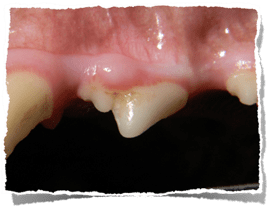

Fibrous hyperplasia in response to plaque and tartar at the gingival margin

- Focal fibrous hyperplasia. Reactive gum tissue may occur in response to chronic periodontal disease and may affect single or multiple teeth. Routine dental care and oral home care are beneficial in preventing recurrence.